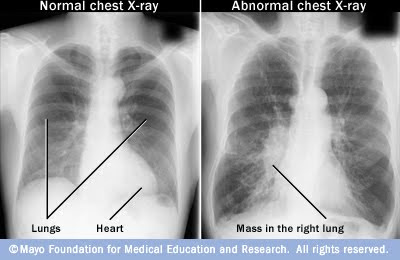

X-ray (Radiography) - Chest - RadiologyInfo.org

ABC’s Of Chest X-rays ABC’s Of Chest X-Rays

Common conditions (i.e. pneumonia, heart failure, intestinal obstruction and fractures). The aim of this “This is a posterior-anterior chest x-ray of GC, born on 06/02/98 and taken on 25/02/01. It is well centred, the whole chest was not captured, it is over-pene-trated, ... Get Content Here

Chest Radiograph - Wikipedia, The Free Encyclopedia

Pneumonia and congestive heart failure are very commonly diagnosed by chest radiograph. additional imaging of the chest can be obtained to definitively diagnose the condition or to provide evidence in favor of the diagnosis suggested by initial chest radiography. ... Read Article

Chest x-ray - Simple English Wikipedia, The Free Encyclopedia

Congestive heart failure; Bone fracture; Hiatal hernia; Pneumonia and congestive heart failure are commonly diagnosed by chest radiograph. Chest x-rays are used to screen for job-related lung disease, for example in mining where workers breathe dust. ... Read Article

Chest X-rays Before Surgery - Consumer Health Choices

To get a pre-op chest X-ray. It can show medical problems, like an enlarged heart, congestive heart failure, or fluid around the lungs. These could mean Chest X-rays before surgery When you need one and when you don’t M ... Fetch Document